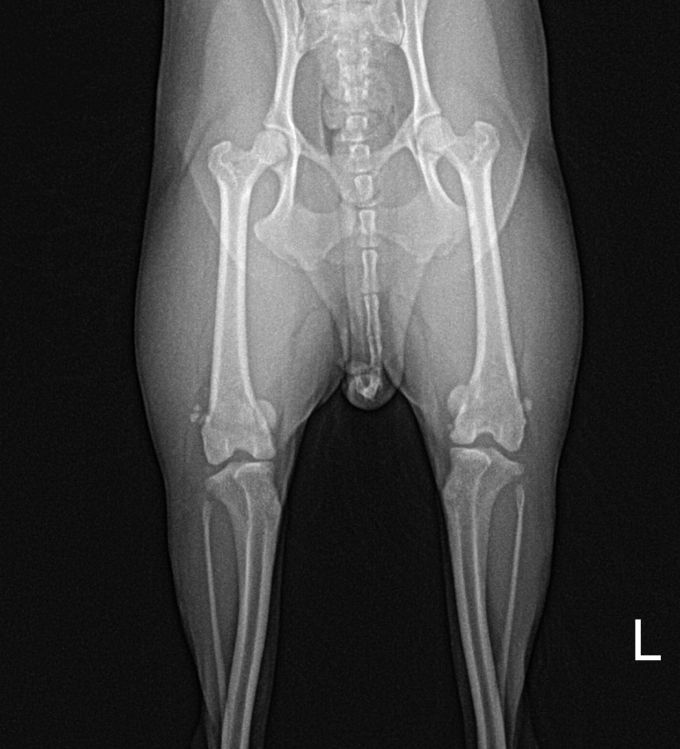

BEFORE

AFTER